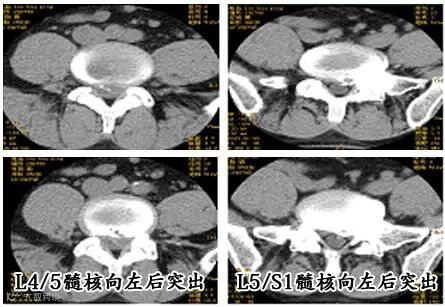

患罗某某,男,50岁,因"反复腰痛7年,伴左下肢放射痛6个月加重1个月"入院。查体:脊柱侧弯,L4/5、L5/S1左侧间隙压痛、叩击痛,向左下肢放射,腰椎活动受限;左足第一趾伸肌肌力Ⅰ级,踝关节背伸肌群肌力Ⅱ肌,左小腿外侧及足背皮肤感觉减退,左下肢直腿抬高试验40度阳性,加强试验阳性。腰椎CT示:L4/5、L5/S1椎间盘局部向后偏左突出。诊断:L4/5、L5/S1腰椎间盘突出症。硬膜外麻醉下对患者采用单切口行椎间盘镜下L4/5、L5/S1椎间盘髓核摘除术,术后第2天患者腰痛即明显缓解,左下肢感觉肌力基本恢复正常,可戴腰围下地活动。